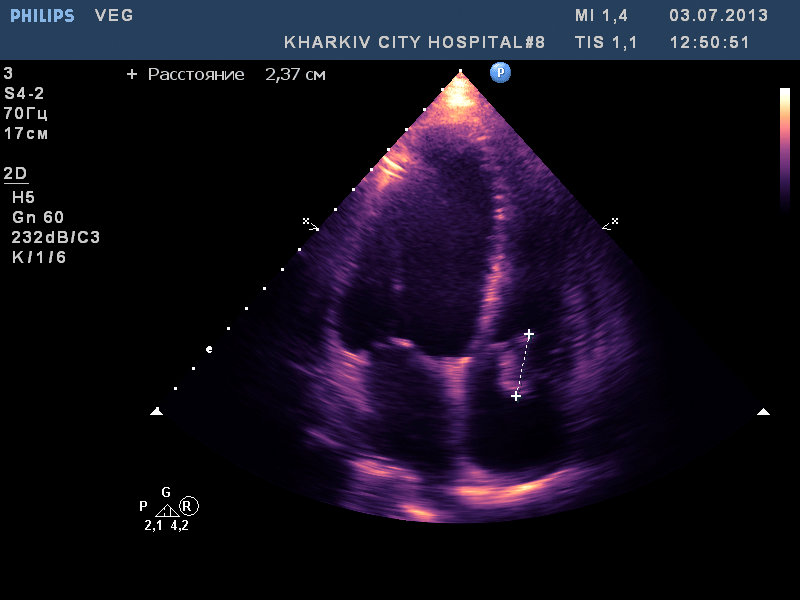

вегетации на АК, МК и ТК

молодой 37лет, с гепатитом C, возможно имеет место быть ВИЧ. по виду наркоман с конкретным стажем